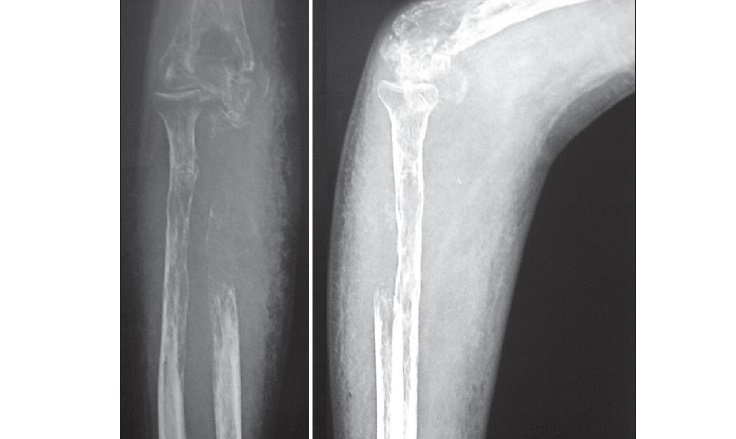

Визуальные материалы, связанные с болезнью Горхема-Стаута

Раздел: Альбом открытий